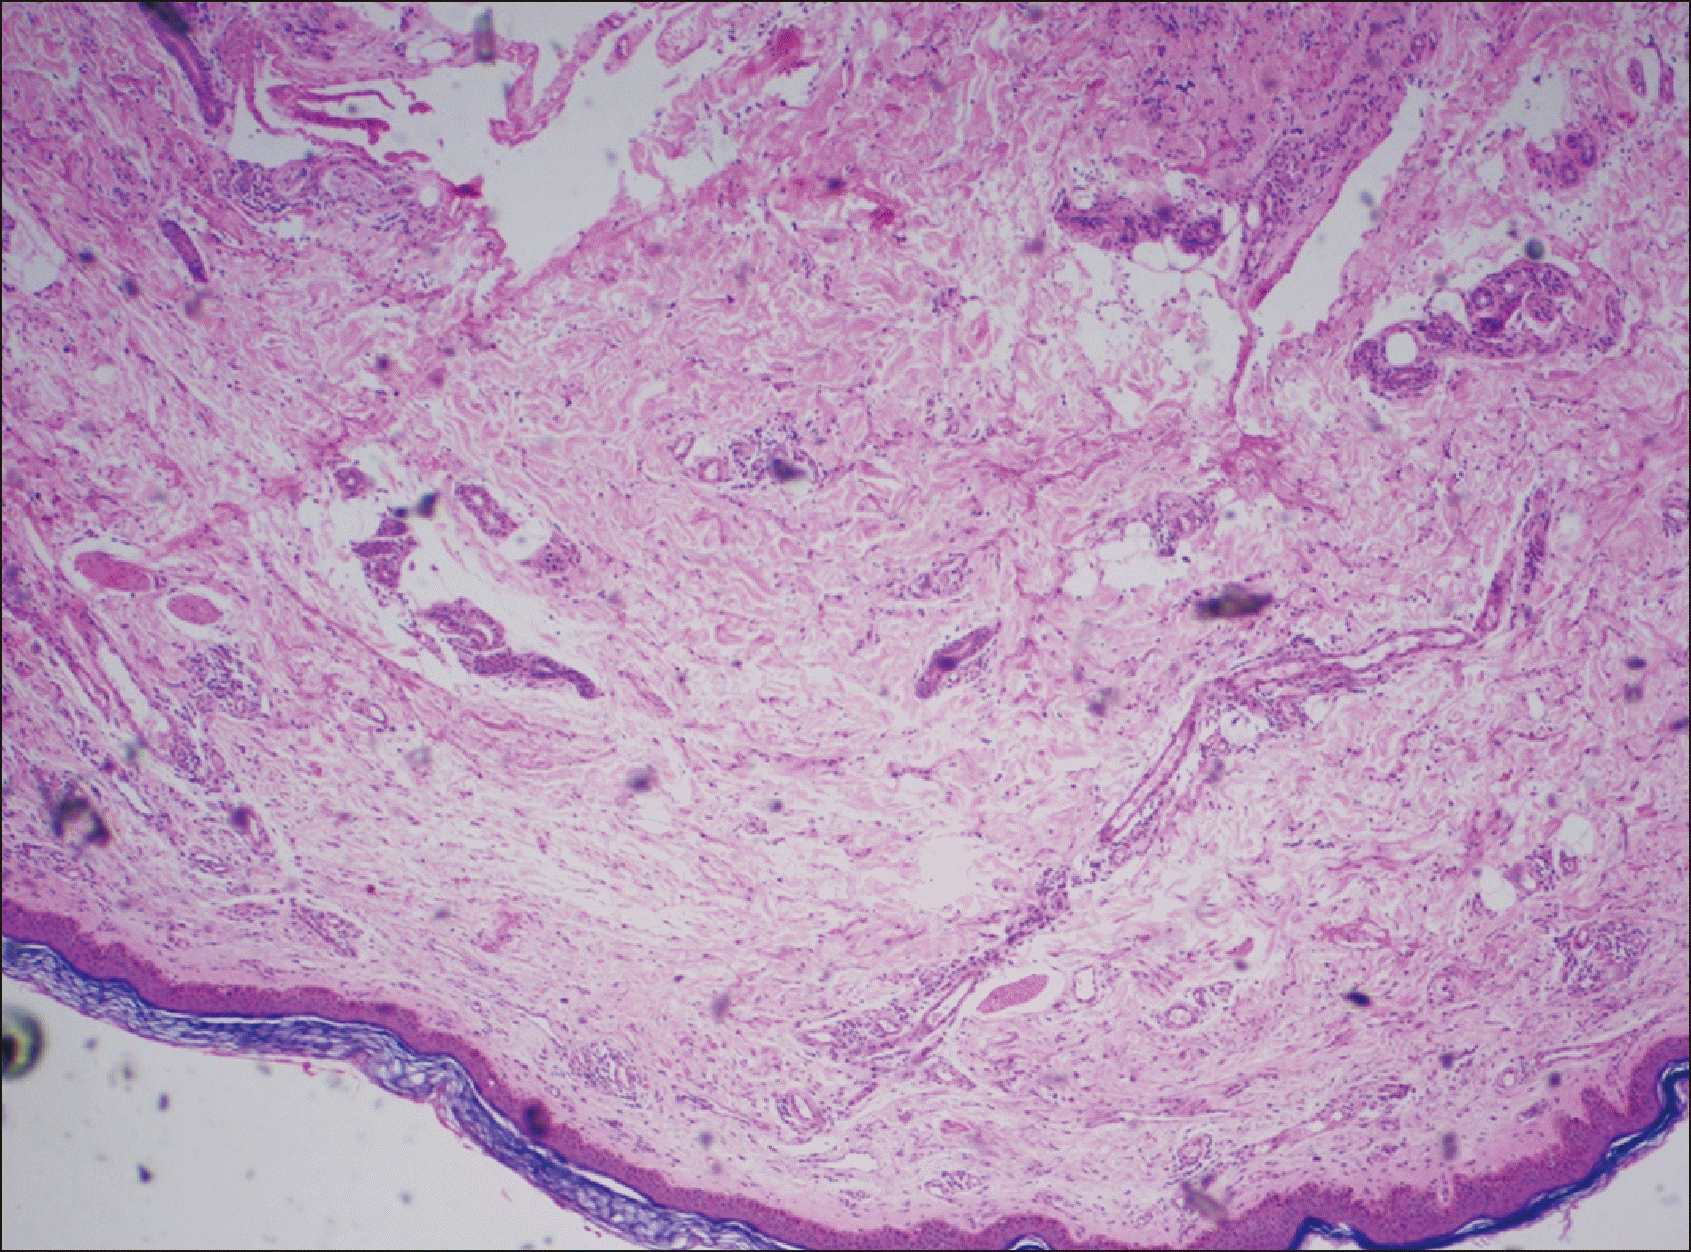

Figure 3

Histopathology image (stain H&E, magnification x100). Epidermis shows keratinisation, flattening of rete ridges, and acanthosis; upper dermis shows inflammatory infiltrate comprising of lymphocytes, plasma cells, and eosinophils and fibrosis of sweat glands; and subcutis shows septal lymphocytic infiltrate with few eosinophils.